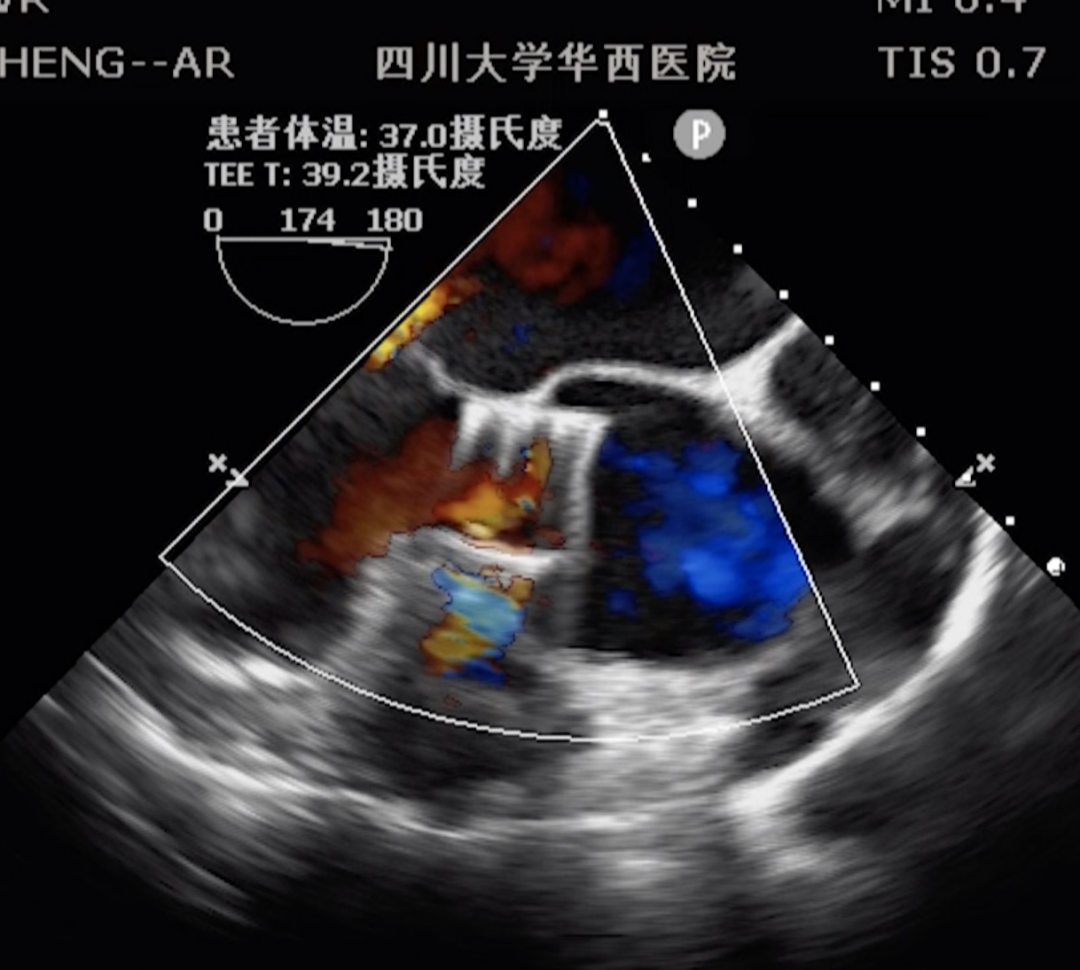

今天第三台J-Valve TAVR手术来自四川大学华西医院郭应强教授带领的多学科心脏团队,充分展现了J-Valve®在单纯主动脉瓣关闭不全经导管治疗治疗方面的独特性和巨大优势,郭应强教授毫无保留的分享了TAVR手术过程中手术的要点,处理心脏荷包的心得体会以及手术过程中团队配合导丝导管技术经验,获得与会专家一致好评。 手术在华西医院杂交手术室内完成,透视下选择心尖处肋间切开,TEE及DSA引导下行心尖穿刺,经心尖送入29mm J-Valve介入瓣膜并进行释放,瓣膜在定位件引导下进入主动脉瓣区域,释放瓣膜,造影及TEE现实瓣膜位置良好,无瓣周漏。从输送瓣膜到成功释放,整个过程不超过5分钟,手术全程患者生命征平稳,无出血,术后心脏功能明显好转,患者快速清醒,手术室内完成拔管,堪称一台J-Valve®介入瓣膜教学级的完美演绎。 下半场手术直播由空军军医大学附属西京医院徐学增教授,华中科技大学同济医学院附属同济医院魏翔教授,武汉亚洲心脏病医院华正东教授,浙江省人民医院崔勇教授,解放军总医院第一医学中心杨明教授,华中科技大学同济医学院附属协和医院陈澍教授共同主持。